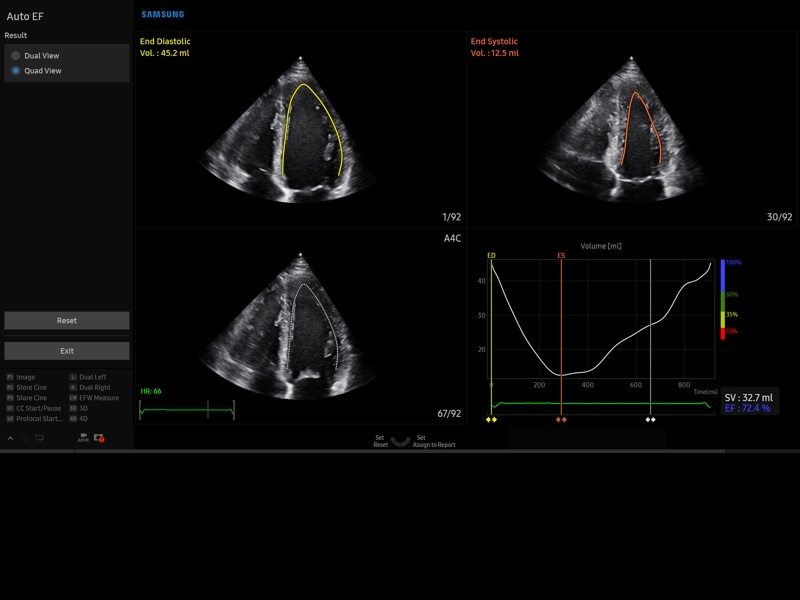

• МодульStrain+- программа не векторной оценки степени сократимости миокарда с выведением автоматически расчетов и графиков на экране отдельно по каждому сегменту.

М-режим:измерение диаметра аорты, передне-заднего размера ЛП, толщины МЖП (систолическая и диастолическая), толщины ЗСЛЖ (систолическая и диастолическая), размеров ЛЖ и ПЖ (систолический и диастолический), ФВ (Teichholz).

B-режим:измерение диаметра аорты (восходящей, дуги, нисходящей, на уровне синусов Вальсальвы, на уровне створок аортального клапана), определение размеров ЛП и ПП (максимальный, минимальный, систолический, диастолический, переднее-задний, верхнее-нижний, медиально-латеральный), расчет объемов ЛП и ПП, объемов ЛЖ (метод "Площадь-Длина", метод дисков (Simpson)), массы миокарда ЛЖ, индекса массы миокарда ЛЖ.